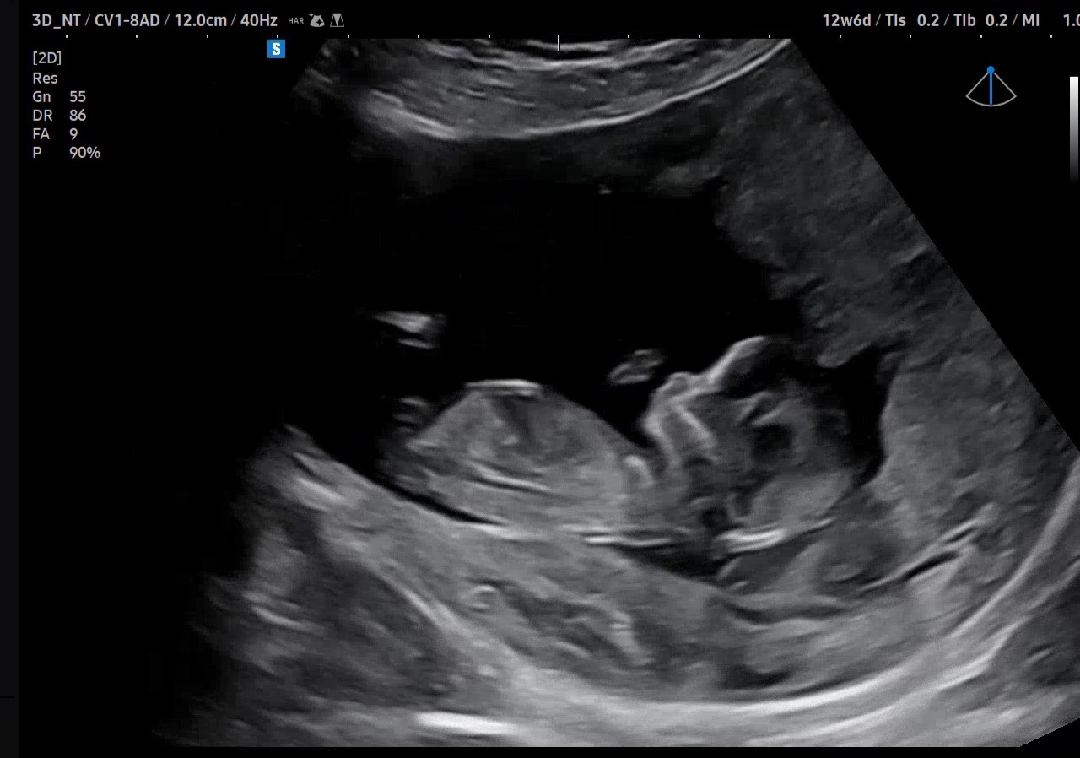

생식기가 나온 사진이여야해요 ㅎㅎ

각도법 고수님들..한번만 봐주세요!!!🙏

저는 진짜 암만봐도 어딜 보라는건지 모르겠거든요.. 한번만 같이 봐주세요!!

생식기부분이 안나온 사진이라 각도법 볼수없어요~